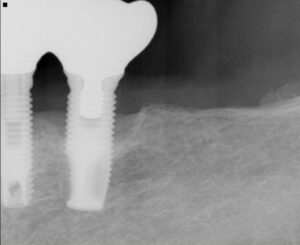

インプラント周囲疾患

- 粘膜炎:約40%

- 周囲炎:約20%

これは天然歯の歯周病と似た炎症です。

実際インプラント周囲の骨がなくなっています。